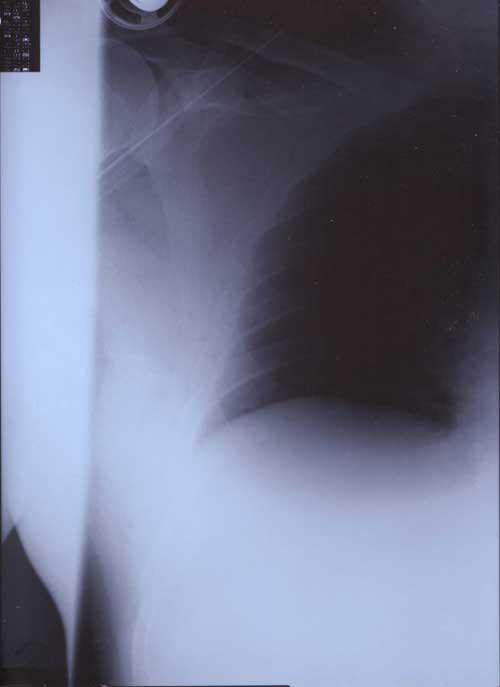

X Rays

21st January 2000